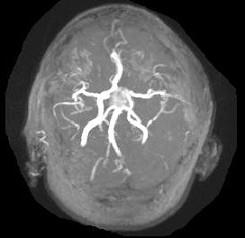

问题 男性,55岁,头痛1年余,2个小时前突然出现剧烈头痛,MRI检查如图所示,最可能的诊断为()

选项 A.垂体瘤 B.脑膜瘤 C.颅咽管瘤 D.垂体瘤并卒中 E.动脉瘤

答案 D